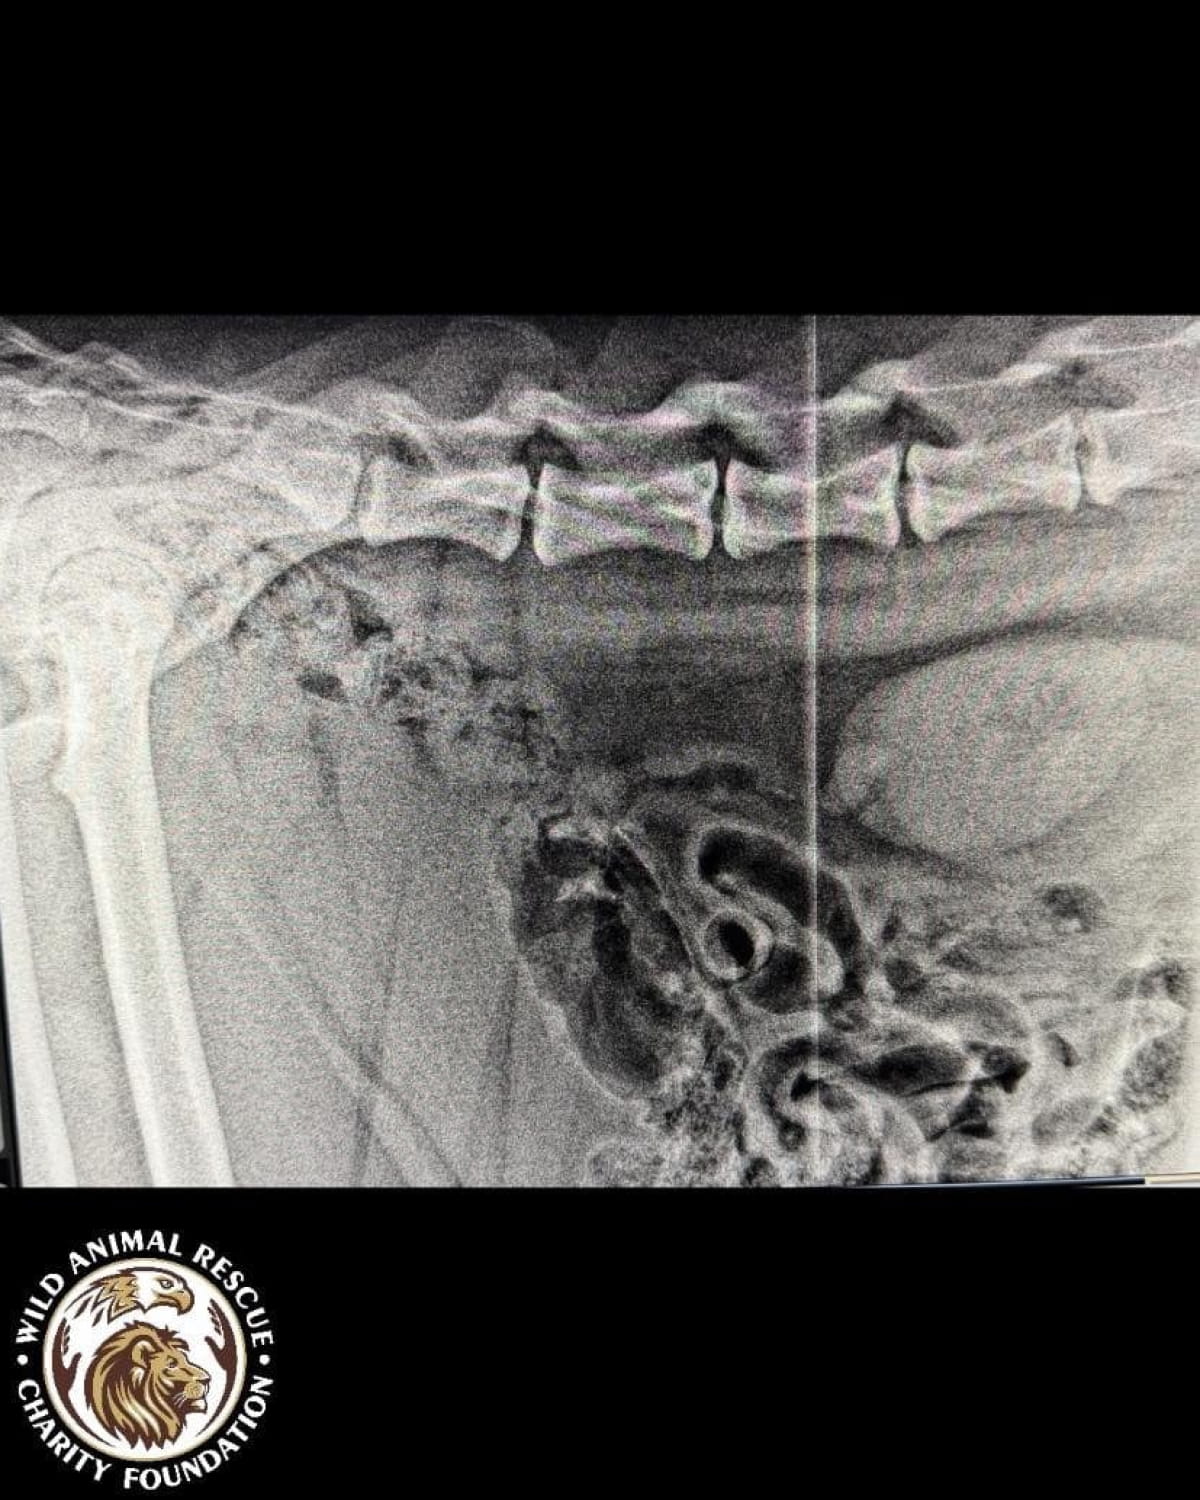

Тварині лише рік, але вона вже стала глибоким інвалідом. Тигриця не здатна самостійно підвестися і ледве пересувається, спираючись виключно на передні лапи. Після ретельного обстеження ветеринари були шоковані станом кісток молодого хижака.

• Критична атрофія м’язів та рахіт.

• Дегенеративні зміни у хребетному стовпі.

• Загальна деформація кісток скелета.

• Двобічна дисплазія кульшових суглобів.

• Остеоартроз та патологічне ремоделювання головки стегнової кістки.

Лікарі утримуються від оптимістичних прогнозів. Процес лікування ускладнюється великою масою тіла хижака та сильною крихкістю кісток, які просто не витримують навантаження. Оскільки тигриця фізично не може довго лежати нерухомо, терапія стає справжнім викликом.

Наразі українські волонтери ведуть активні перемовини із закордонними експертами, щоб підібрати найменш болісний курс лікування. Проте дива не станеться: навіть за найуспішнішого сценарію деякі зміни у скелеті є незворотними. Тварина вже ніколи не стане повністю здоровою і до кінця свого життя потребуватиме спеціальних умов та постійної підтримки.